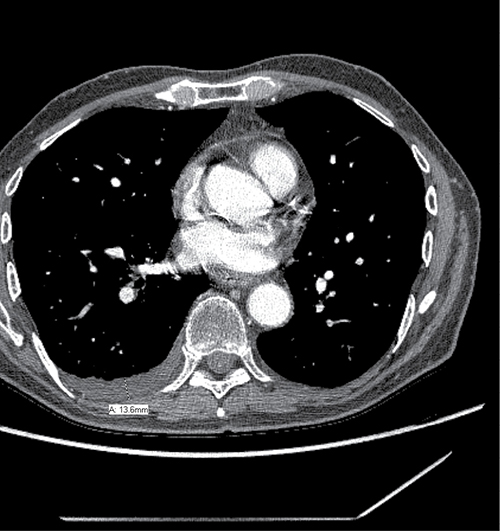

The diagnosis of pleural effusion was independently assessed by one physician, and was spot checked by another physician. Several previous studies reported models based on simple measurement from the chest radiographs to estimate the volume of pleural effusions [38–41]. Patients with fluid loculation were not excluded. We selected the model from Hazlinger, et al. [40], who reported the dimension of effusion depth as the best planar measurement which was significantly correlated with the actual PE. The model described by Hazlinger, et al., estimates the PE volumes from CT scans using the formula: the volume of PE = 0.365 × b3 – 4.529 × b2 + 159.723 × b – 88.377, where b was the depth measured perpendicularly to the parietal pleura on transversal CT scan where the greatest depth was found by scrolling through all the images [40]. An example of measurement is shown in Figure 1. New pleural effusion or increased volume of PE after TRT without evidence of tumor progression was considered to be RIPE. To determine the most relevant dose-volume parameter, a receiver operator characteristic (ROC) curve was constructed. The Youden Index was used as the optimal cutoff from the curve, which is defined as sensitivity + specificity-1.

Figure 1: Example measurement for radiation induced pleural effusion.

RIPE of any grade developed in 51 (29.1%) patients, in which 39 patients had newly developed PE after TRT without disease progression and the remaining 12 patients had PE increases after TRT. The median (range) change of PE depth was 13.6 (2–90.6) mm, and the median (range) change of estimate PE volume was 2164.3 (215.9–248,649) ml. The median (range) RIPE interval from end of TRT was 3.7 (0.6–18.0) months. Forty patients developed symptomatic RIPE; 24 of these patients (60.0%) presented with chest pain; 12 (30.0%) suffered from cough; and 18 (45.0%) had shortness of breath or dyspnea. The actuarial incidence of RIPE at 1 and 2 years for those 51 patients was 88.8% and 11.2%, respectively. The RIPE rates of the two institutions in all patients were 22.6% and 38.6% with a borderline significance in difference (p = 0.055).